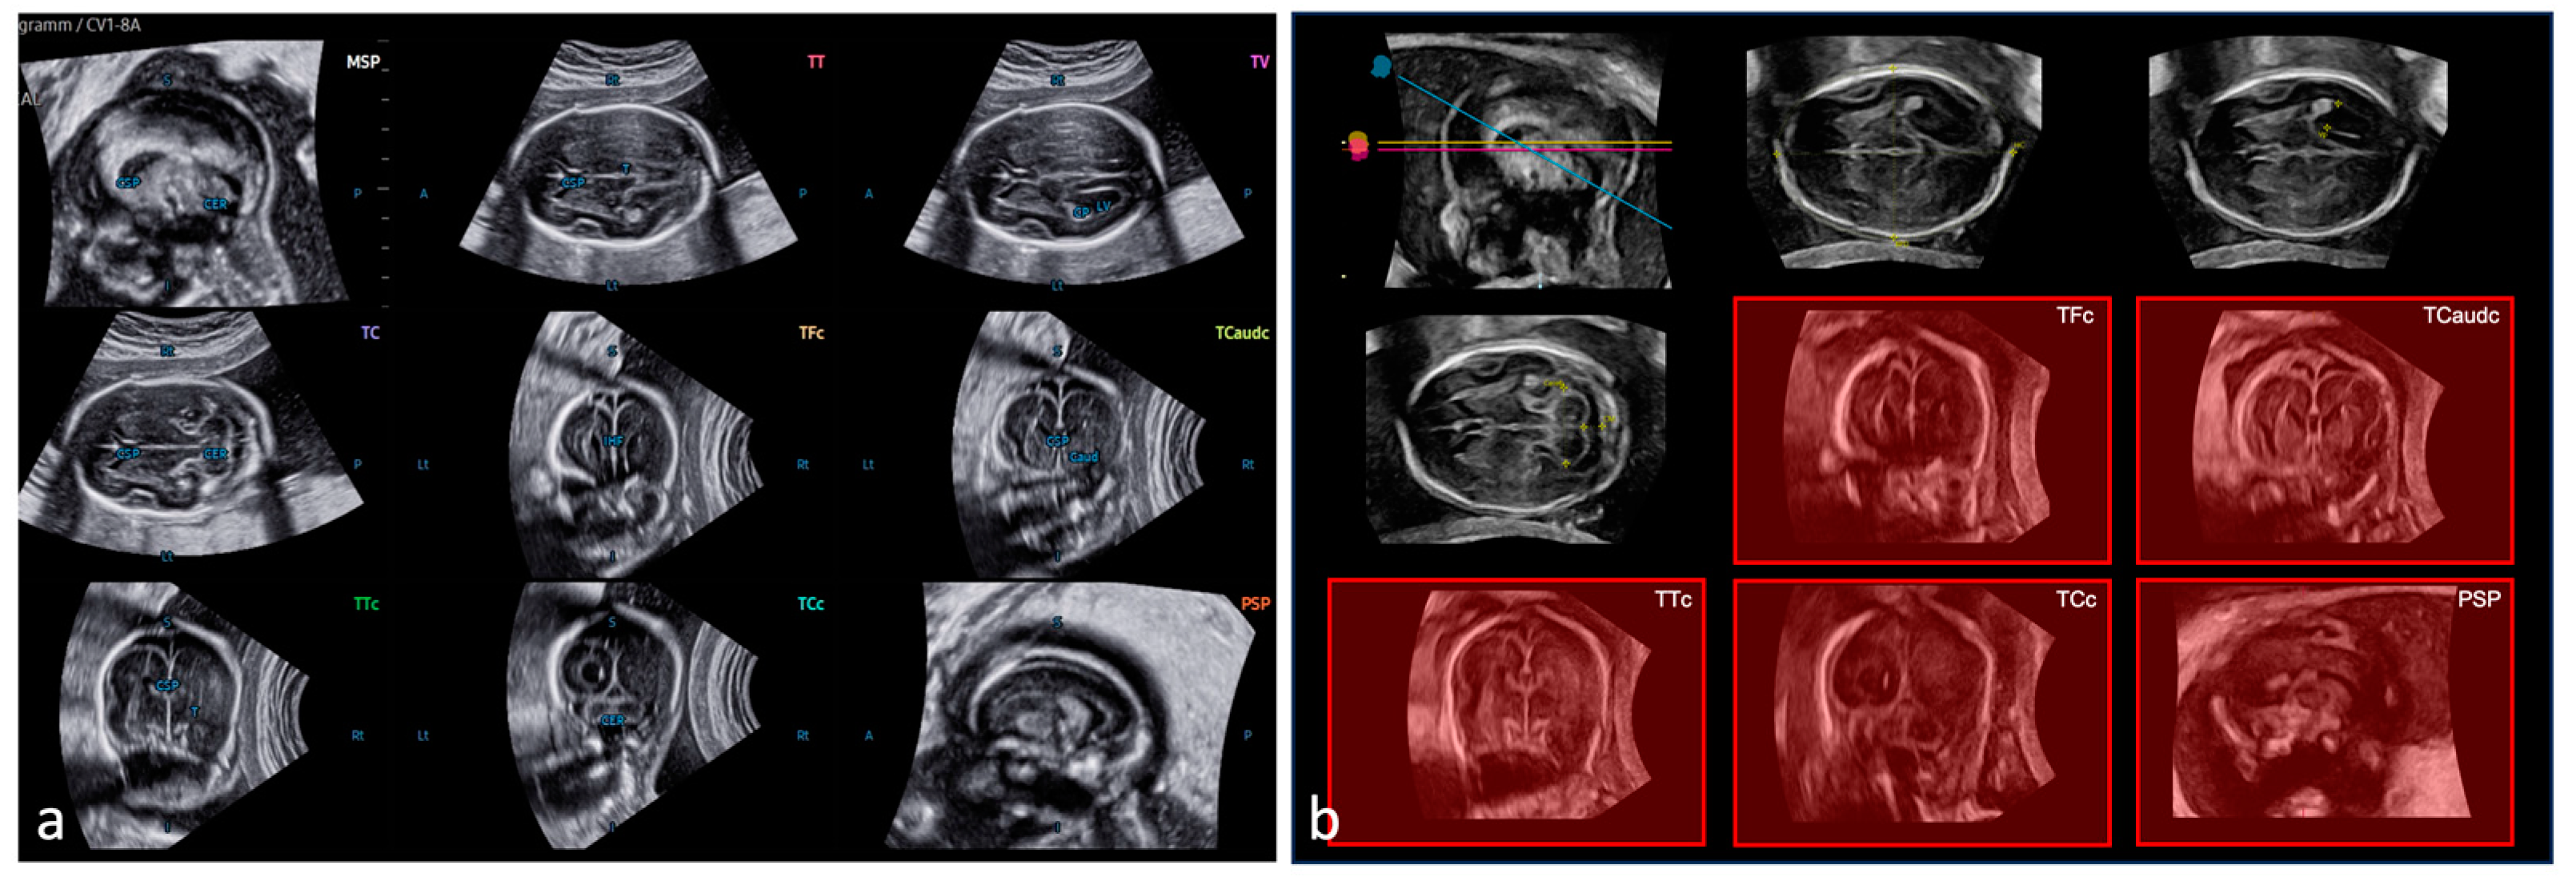

2.2. SonoCNS™

2.3. 5DCNS+™